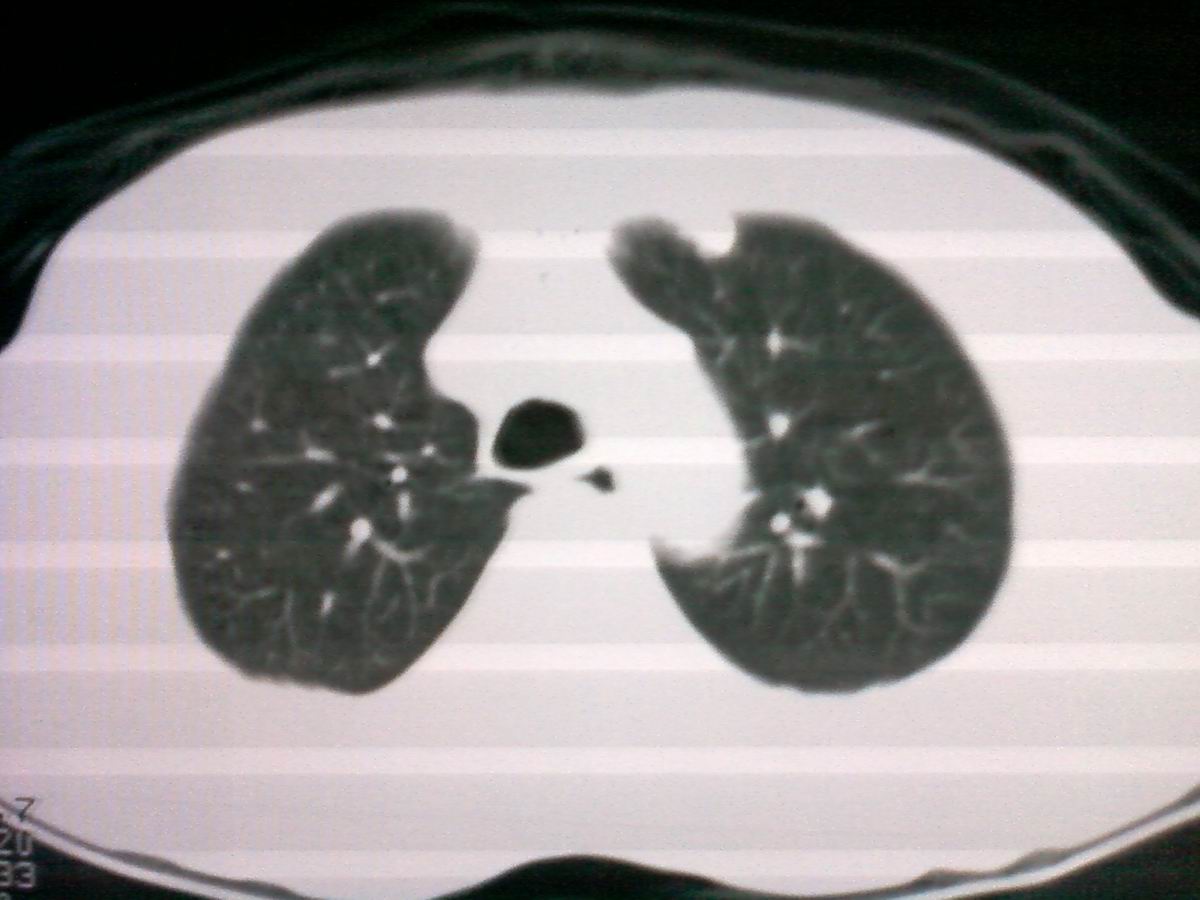

支持气管内恶性肿瘤,建议支气管镜活检。

先咳一下,看看是否痰栓再考虑占位。

气管有占位鳞癌、腺样囊性癌、类癌、粘液表皮样癌。